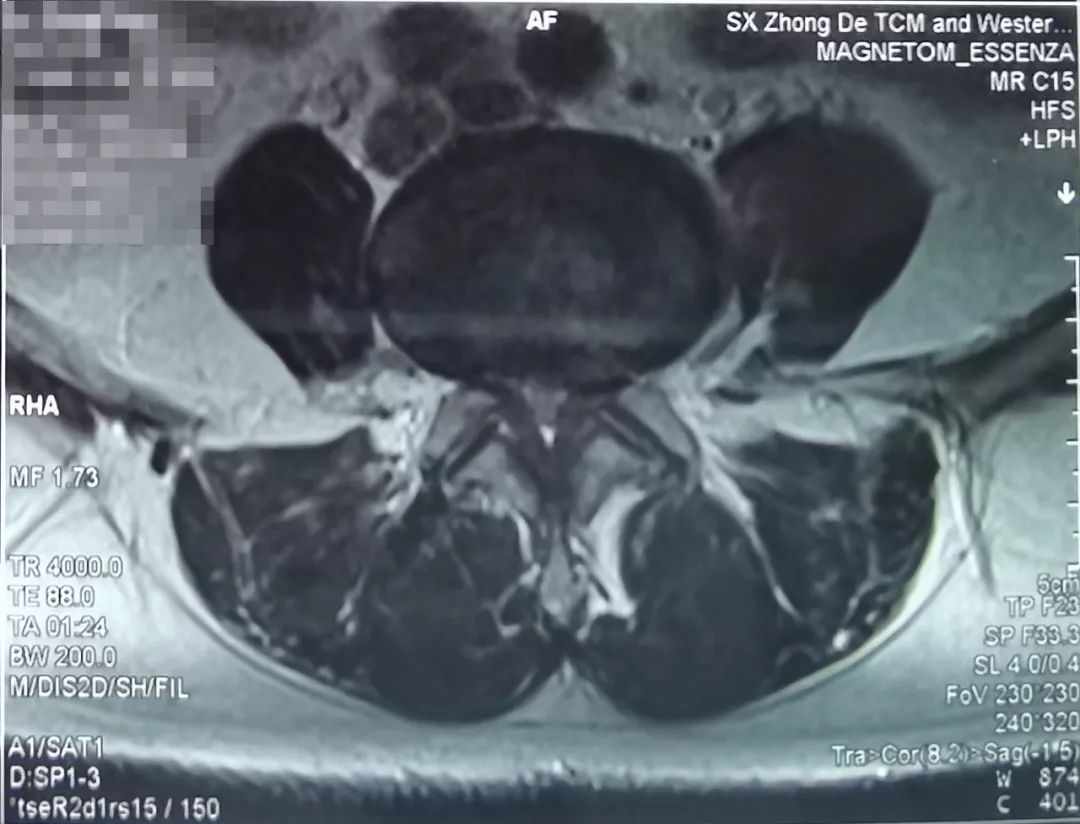

患者,女,63岁,主诉近期腰疼,双腿抽痛、麻木。之前在当地医院保守治疗1个月,效果不明显。

了解患者病情及影像学资料、仔细查体后,空军军医大学唐都医院骨科脊柱病区李晓祥博士诊断患者为腰椎间盘突出症、腰椎管狭窄症,并建议进行微创手术治疗。

像上面这样的患者出现症状影响生活,并且从影像学资料上看突出造成严重的腰椎管狭窄,已经压迫到神经,经过保守治疗后效果不好,这种情况就可以考虑手术治疗。